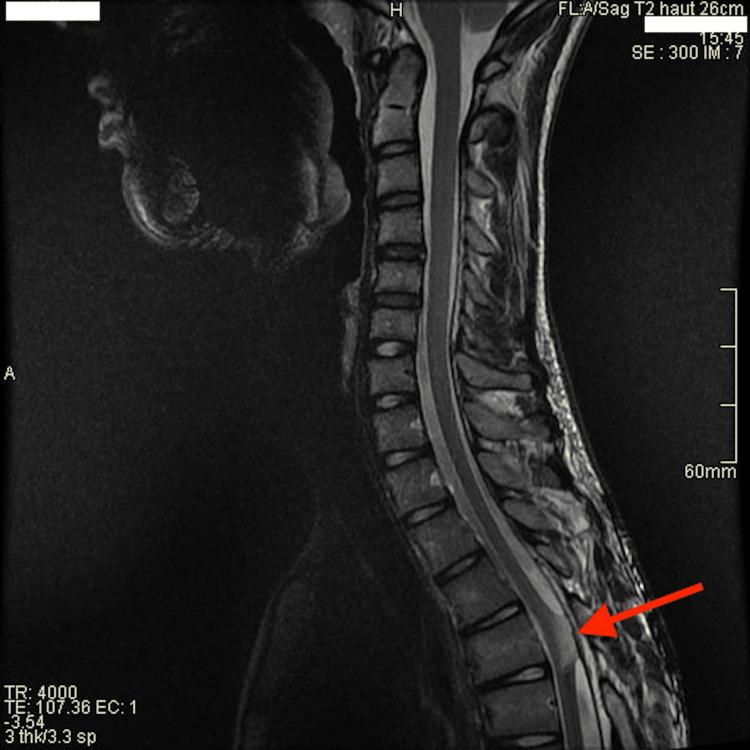

We present a case of a 13-year-old boy with abdominal pain initially misdiagnosed as gastrointestinal in origin. Despite initial outpatient management, his symptoms rapidly deteriorated, revealing a central-medullary cavernous malformation causing spinal cord compression. This case underscores the importance of a comprehensive pediatric examination and highlights new treatment approaches for spinal cavernous malformations.

我们报告一例13岁男孩,最初因腹痛被误诊为胃肠道疾病。尽管最初进行了门诊治疗,但其症状迅速恶化,结果发现是中央髓内海绵状血管畸形导致脊髓受压。该病例强调了全面儿科检查的重要性,并突出了脊髓海绵状血管畸形的新治疗方法。